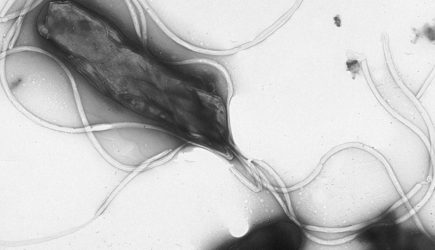

По словам врача, часто к раку желудка приводят воспаления слизистой оболочки этого органа. «Наиболее изученным фактором риска является инфекция Helicobacter pylori, которая может приводить к формированию атрофического гастрита, кишечной метаплазии и другим предраковым изменениям», — предупредил Бамматов.